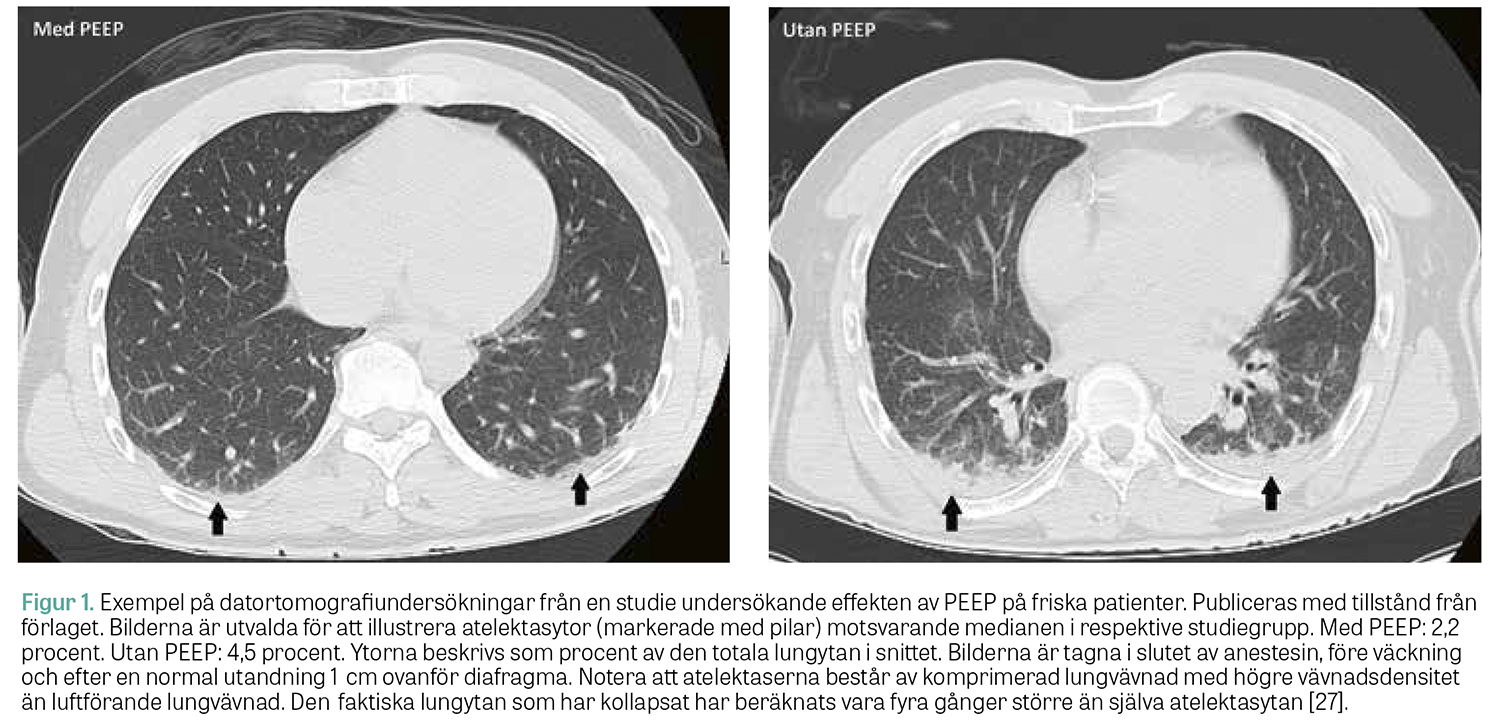

Vid mekanisk ventilation av sjuka/inflammerade lungor (i synnerhet vid ARDS) är lungrekrytering nödvändig för att kunna öppna upp sammanfallna lungavsnitt och förbättra gasutbytet i lungan. Vid anestesi av patienter med friska lungor är situationen annorlunda. Evidensläget är dock fortfarande otillräckligt för att kunna ge tydliga rekommendationer kring när, hur och hos vilka patienter som rekryteringsmanöver  bör utföras [26]. En klinisk situation då lungrekrytering vanligen blir aktuell är när kraftigt överviktiga patienter opereras, i synnerhet vid större kirurgi. I gruppen friska, normalviktiga patienter som genomgår icke bukkirurgi har däremot flera studier från vår forskargrupp visat att rutinmässiga rekryteringsmanövrar inte behövs, utan enbart ett måttligt PEEP räcker för att lungorna ska vara i princip rena från atelektaser i slutet av anestesin, se Figur 1 [27]. Sannolikt verkar PEEP i detta sammanhang förebyggande om det appliceras tidigt, innan atelektaserna utvecklats till fullo. Möjligen har ett måttligt PEEP även en viss egen rekryterande effekt, förutsatt att lungvävnaden i övrigt är frisk och att atelektaserna är relativt nybildade. I Fakta 3 presenteras en strategi för att minimera atelektasutveckling under anestesi hos låg­riskpatienter.

Figur 1.